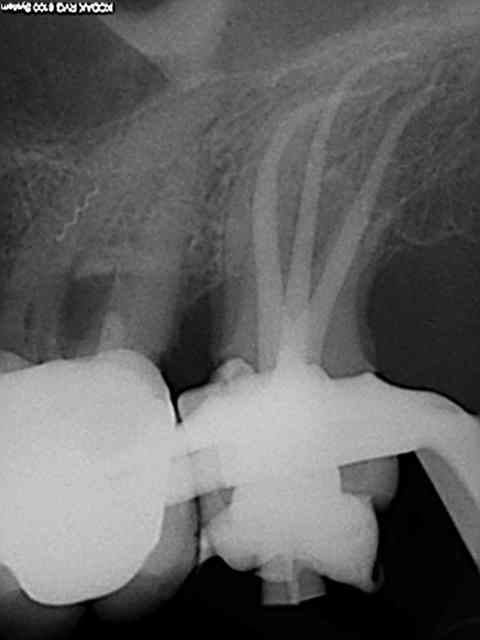

Et une de plus !

R19 vxiysf - Eugenol

R20 kboz6l - Eugenol

C'est pas de la frime hein, mais ca fait plaisir d'avoir trouvé ENFIN une technique rapide et reproductible sans casse. (enfin presque il y a dans le tas un micro morceau de R25 pas loin de l'apex )

Bravo ! Belles images